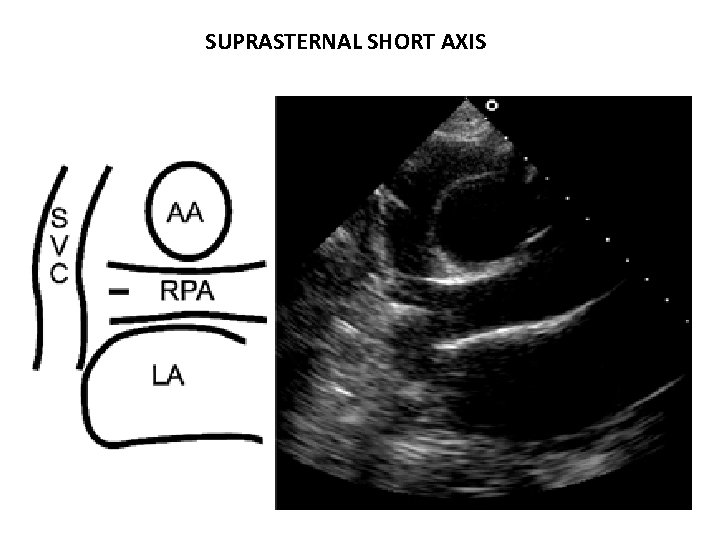

SUPRASTERNAL SHORT AXIS